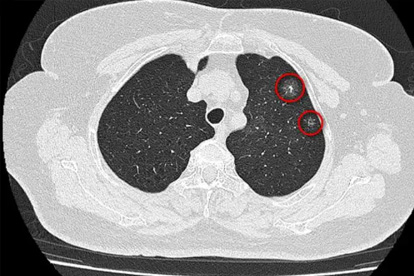

肺癌的发病原因复杂,与吸烟、空气污染、职业暴露、遗传因素等密切相关。早期诊断和规范治疗对提高患者生存率至关重要,因此选择专业医院尤为重要。

肺癌预防需要从日常生活做起,戒烟是重要的预防措施。避免接触二手烟、厨房油烟等有害物质,职业暴露人群要做好防护。40岁以上人群,特别是有吸烟史者,建议每年进行低剂量CT筛查。保持健康饮食,多摄入新鲜蔬果,适量运动有助于增强免疫力。出现持续咳嗽、痰中带血等症状应及时就医,早发现、早治疗是提高生存率的关键。